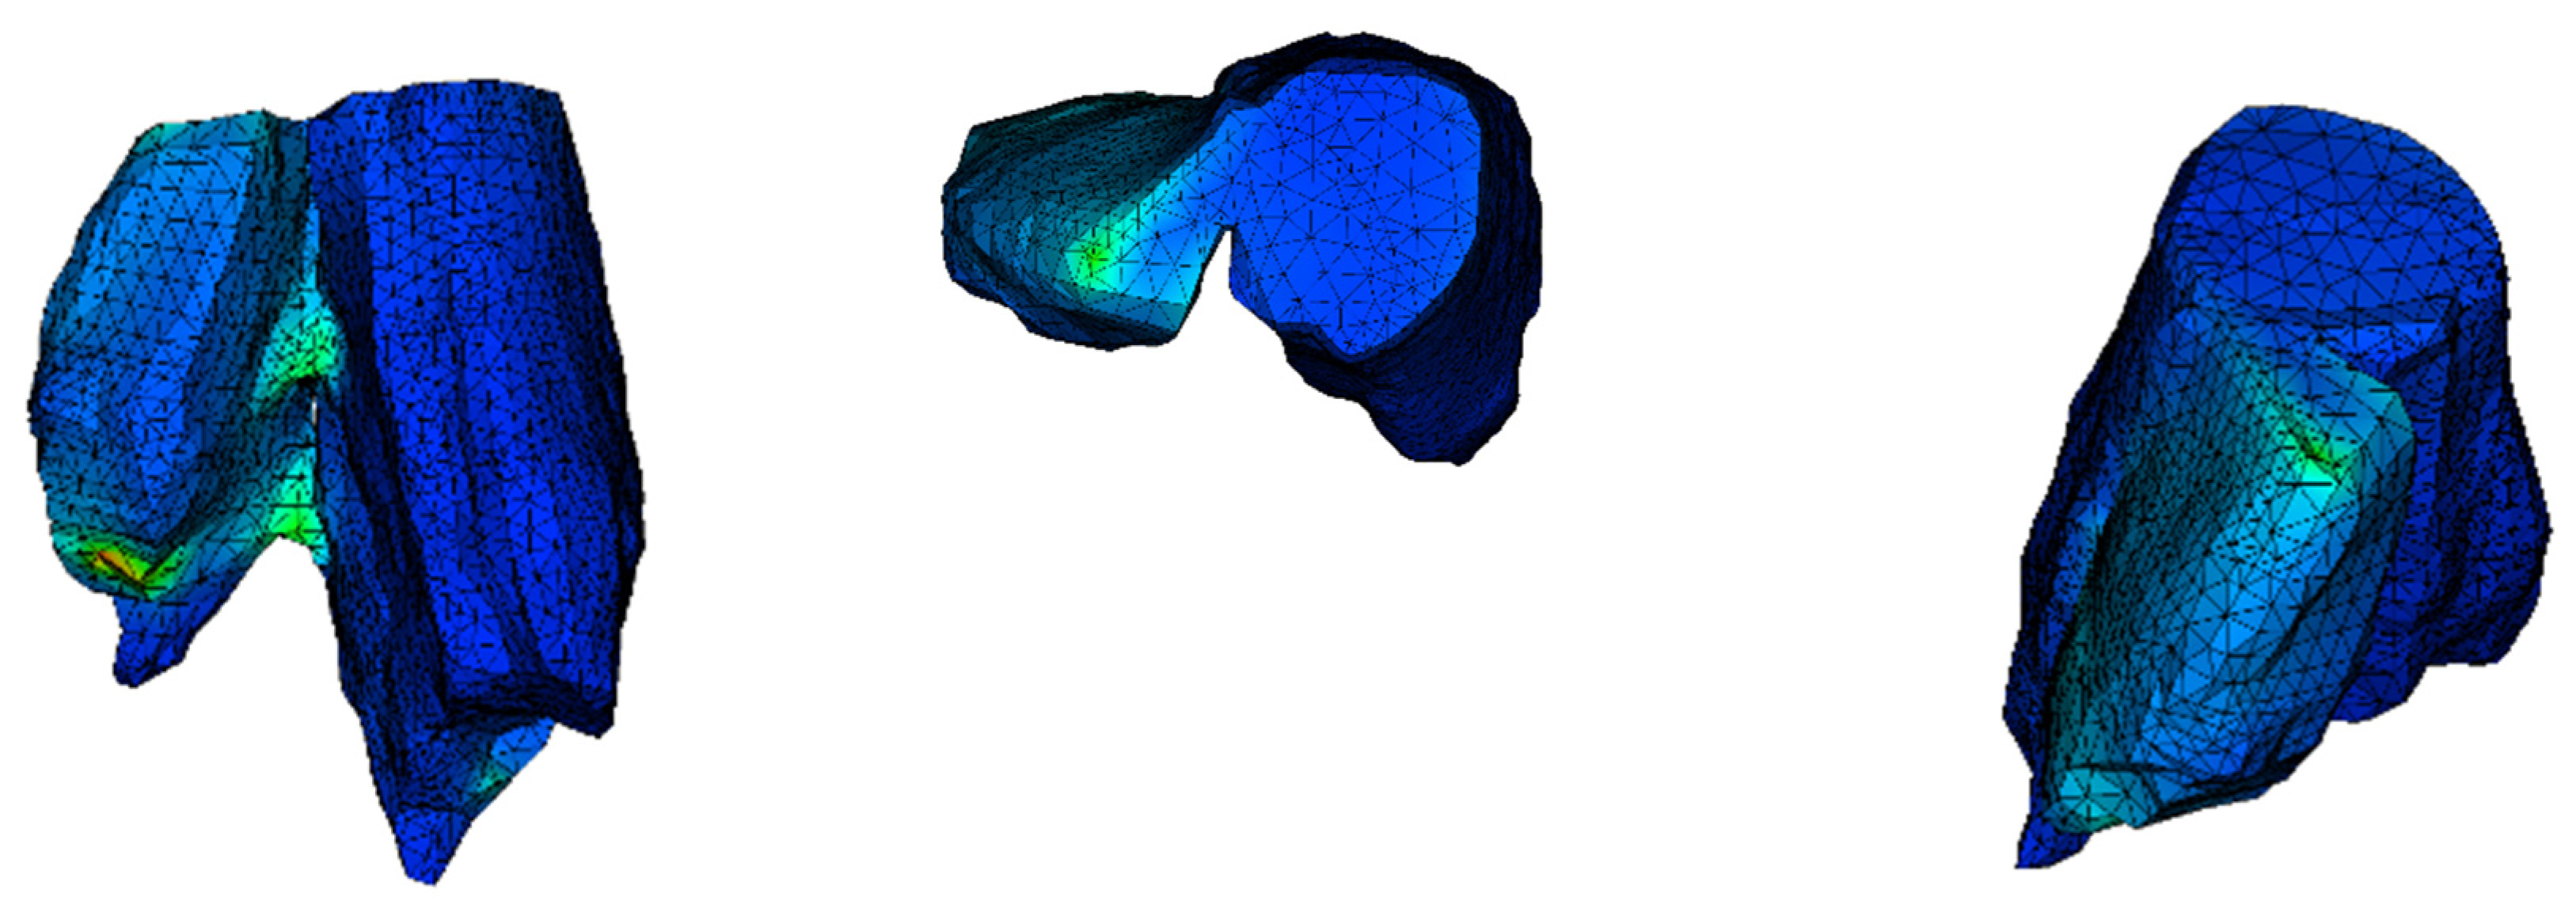

The model of the bone with no treatment fixation applied is delivered to unveil where the maximum stress is concentrated and the dislocation of it under action. It is common in finite element models for the stress to be concentrated where the load is applied. To find and point out the maximum stress, ignoring this local phenomenon, we hide those few elements. The maximum von Mises stress is 196.2 MPa and is found where the two parts of the examined bone are connected. The lack of stability in the system shows the necessity of fixation. The way that the bone tents to split (Figure 6) indicates how the treatment solution should be applied, resisting the separation of the two bone parts. The position where the higher stress is found is highlighted (Figure 7).

Figure 6.

Dislocation of the bone in different perspectives (scale factor 1000).

3.4. Analysis of the PCL Scaffold

Stress distribution appears to be different from the previous two simulations. The display tool is changed to stress on node instead of stress on element. Additionally, as the mesh was quite fine in this analysis, it is not shown. The simulation of the scaffold follows the exact geometry of the implant as defined in Rhino software. The intent is to visualize the stress distribution in the scaffold model in order to improve its design. A simplified approach could be followed by applying the homogenized approach. Stress can be transferred from the broken part to the other one through the scaffold (Figure 8). The maximum stress is greater than the strength of the scaffold (Table 3). According to these analysis results, a PCL scaffold could not be a treatment solution for a fracture like this, although it could possibly have a beneficial impact if it was combined with screws. The core function of a scaffold like this is the acceleration of cell growth.

Figure 8.

Maximum von Mises stress in MPa.